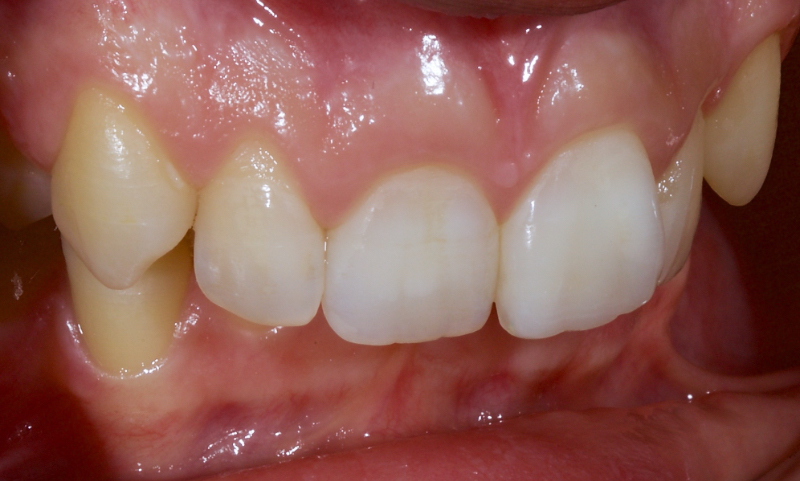

Historically, discolored anterior teeth were treated with indirect ceramic restorations, such as crowns or veneers. This can be illustrated in the case shown in Figure 1, where the discolored left central incisor (2.1), along with two other incisors, was treated with lithium disilicate ceramic veneers (Fig. 2). More recently, direct composite materials that incorporate specialized “opaquers” have also been utilized for treatment.